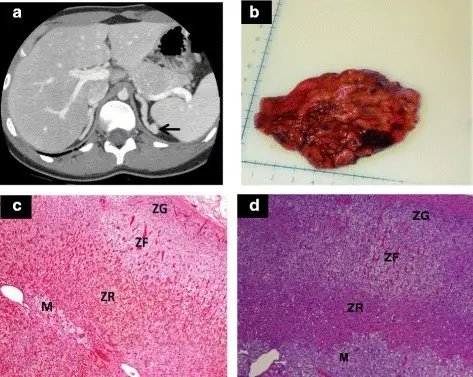

The largest and outermost portion of an adrenal gland is called the adrenal cortex.

The adrenal gland is composed of three distinct zones which include:

- Zona glomerulosa

- Zona fasciculata

- Zona reticularis

Zona glomerulosa produces mineralocorticoids like aldosterone.

Zona fasciculata creates glucocorticoids like cortisol.

Zona reticularis generates sex hormones like testosterone.

Congenital Adrenal Hyperplasia (CAH)

A group of hereditary diseases affecting the adrenal glands, a pair of walnut-sized structures above the kidneys, is known as congenital adrenal hyperplasia (CAH).

Congenital adrenal hyperplasia (CAH) is due to the excess sex steroids with hyperplasia of both adrenal glands.

The most common cause of congenital adrenal hyperplasia is inherited 21-hydroxylase deficiency.

Aldosterone and corticosteroids are made possible by the enzyme 21-hydroxylase.

When an enzyme is lacking, steroidogenesis is primarily diverted toward the creation of sex steroid, which does not require 21-hydroxylase.

Lack of negative feedback from increased adrenocorticotropic hormone (ACTH) secretion brought on by cortisol deficiency causes bilateral adrenal hyperplasia.